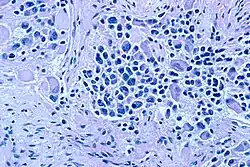

| Microscopic view of a typical neuroblastoma with rosette formation | |

On microscopy, the tumor cells are typically described as small, round and blue, and rosette patterns (Homer Wright pseudorosettes) may be seen. Homer Wright pseudorosettes are tumor cells around the neuropil, not to be confused with a true rosettes, which are tumor cells around an empty lumen.[29] They are also distinct from the pseudorosettes of an ependymoma which consist of tumor cells with glial fibrillary acidic protein (GFAP)–positive processes tapering off toward a blood vessel (thus a combination of the two).[30] A variety of immunohistochemical stains are used by pathologists to distinguish neuroblastomas from histological mimics, such as rhabdomyosarcoma, Ewing's sarcoma, lymphoma and Wilms' tumor.[31]

In 1864 German physician Rudolf Virchow was the first to describe an abdominal tumor in a child as a "glioma". The characteristics of tumors from the sympathetic nervous system and the adrenal medulla were then noted in 1891 by German pathologist Felix Marchand.[76][77] In 1901 the distinctive presentation of stage 4S in infants (liver but no bone metastases) was described by William Pepper. In 1910 James Homer Wright understood the tumor to originate from primitive neural cells, and named it neuroblastoma. He also noted the circular clumps of cells in bone marrow samples which are now termed "Homer Wright rosettes". Of note, "Homer-Wright" with a hyphen is grammatically incorrect, as the eponym refers to just Dr. Wright.[78]